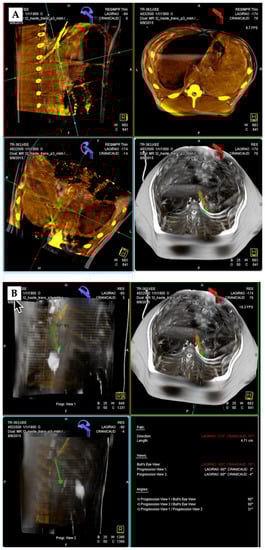

3.2. 3D Angiography-Guided TIPS Procedure Using Pre-Procedural Cross-Sectional Imaging with CBCT/Angiography-Fused Images

3.3. 3D Angiography-Guided TIPS Using CBCT/Angiography-Fused Images

3.4. 3D Angiography-Guided DIPS Using CT/CBCT/Angiography-Fused Images